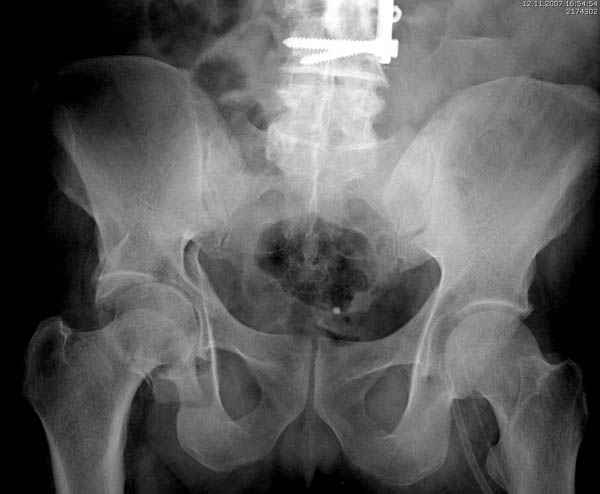

Полную нагрузку разрешаем в 12 недели, хотя движения в суставе с первых дней.

Снимки здесь....